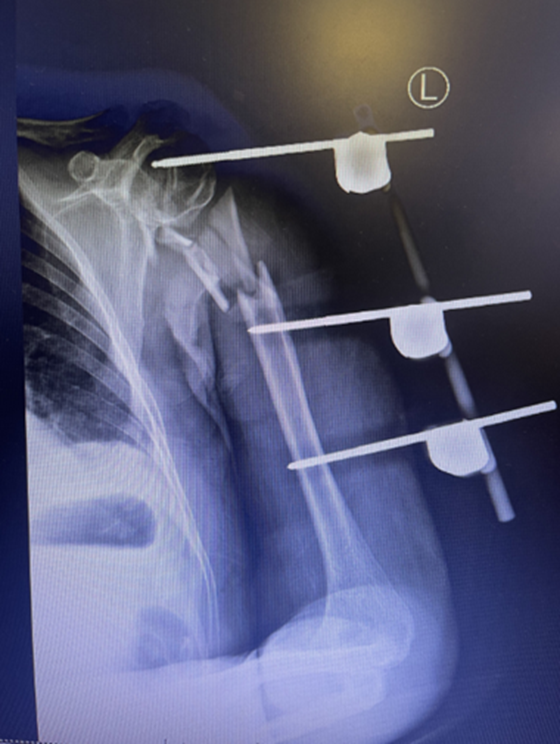

当晚,骨科团队连夜手术,成功探查并修复因骨折压迫形成的血栓栓塞,恢复患者左手血运及温度,同时用外固定架临时固定骨折部位。患者在骨科医护团队的精心照料下顺利出院。

第一次手术:术后外固定支架固定